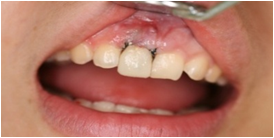

術前口腔内写真術前口腔内写真

歯が割れて唇側に傾いています。

術前口腔内写真